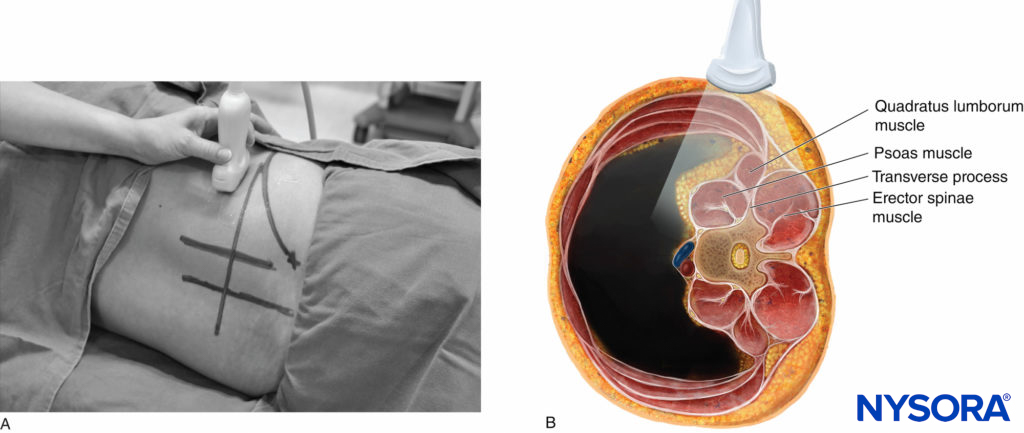

Ultrasound scan for LPB can be performed in the transverse or sagittal axis (Figures 9 and 10) and with the patient in the lateral, sitting, or prone position. A disadvantage of performing LPB with the patient in the prone position is that this position impairs visualization of the quadriceps muscle contraction that is used as an endpoint for needle placement. The author prefers to perform the US scan with the patient in the lateral decubitus position with the side to be blocked uppermost (see Figure 9). The following anatomical landmarks are identified and marked on the skin of the nondependent side of the back: the posterior superior iliac spine, iliac crest, lumbar spinous processes (midline; see Figure 9) and intercristal line (see Figure 9).

A liberal amount of ultrasound gel is applied to the skin over the lumbar paravertebral region for acoustic coupling. To simplify image orientation, irrespective of the side imaged, the orientation marker of the US transducer is directed cranially during a sagittal scan and laterally (outward) during a transverse scan. For a sagittal scan (Figures 9, 10, 11, and 12), the US transducer is positioned over the sagittal scan line (see Figure 9a) with its orientation marker directed cranially. For a transverse scan (Figures 9,10, 13, and 14), the US transducer is positioned 4 cm laterally to the midline along the intercristal line and just above the iliac crest (see Figure 9b). The transducer is also directed slightly medially (paramedian transverse oblique scan [PMTOS]; see Figure 9b) so as to produce a transverse oblique view of the lumbar paravertebral region (see Figures 13 and 14).

FIGURE 15. (A) Position of the patient (lateral decubitus) and US transducer during a transverse scan at the flank for the Shamrock method. (B) US transducer and plane of US beam superimposed onto a transverse anatomical section of the lumbar paravertebral region, illustrating how the US beam is insonated (axis of scan) and structures are visualized during the scan.